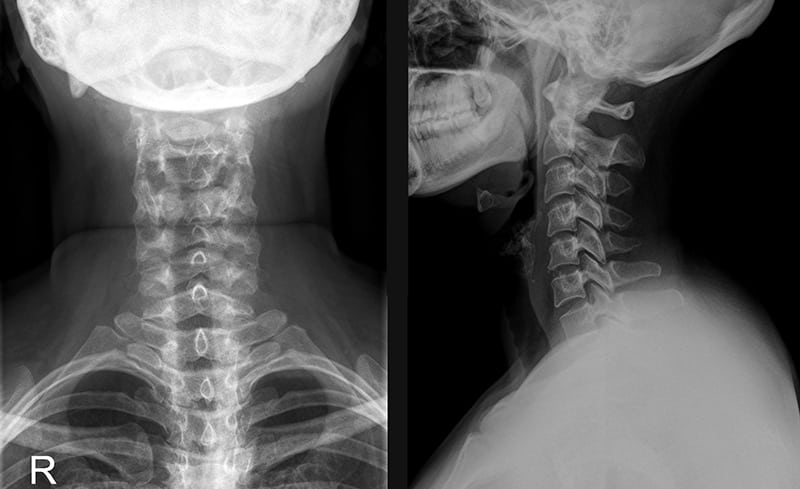

image

Рентген шейного отдела позвоночника.

Для выявления степени повреждения могут использоваться рентгенография, УЗИ, КТ. Наиболее информативная диагностическая методика — магнитно-резонансная томография. В терапии применяются консервативные способы: ношение ортопедических воротников, физиопроцедуры, ЛФК, нанесение на область шеи мазей от растяжений с анальгетическим и противовоспалительным действием.

1. Рентгенография. С его помощью специалист осмотрит не только шею, но и позвоночник. Это поможет определить, не произошли ли в этих местах дополнительные деформации.